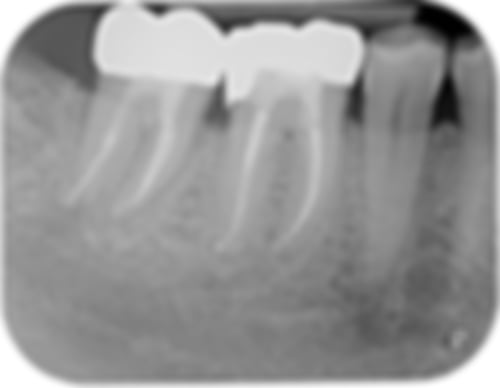

Ist Ihr Zahnnerv entzündet, entfernen wir das erkrankte Gewebe und reinigen den Zahn und die Wurzelkanäle sorgfältig, um Bakterien, die die Entzündung hervorrufen, nachhaltig zu entfernen. Im nächsten Schritt füllen wir die Wurzelkanäle und versiegeln den Zahn. So wird einer neuerlichen Infektion vorgebeugt und der Zahn kann noch lange erhalten bleiben.

Ziel dieser Maßnahme ist es, den stark entzündeten oder toten Zahnnerv zu entfernen, das Innere des Zahnes zu säubern und die gereinigten Wurzelkanäle danach wieder zu füllen. Gerade unbehandelte Entzündungen können weitere Infektionen von Knochen und Gewebe im Körper auslösen.